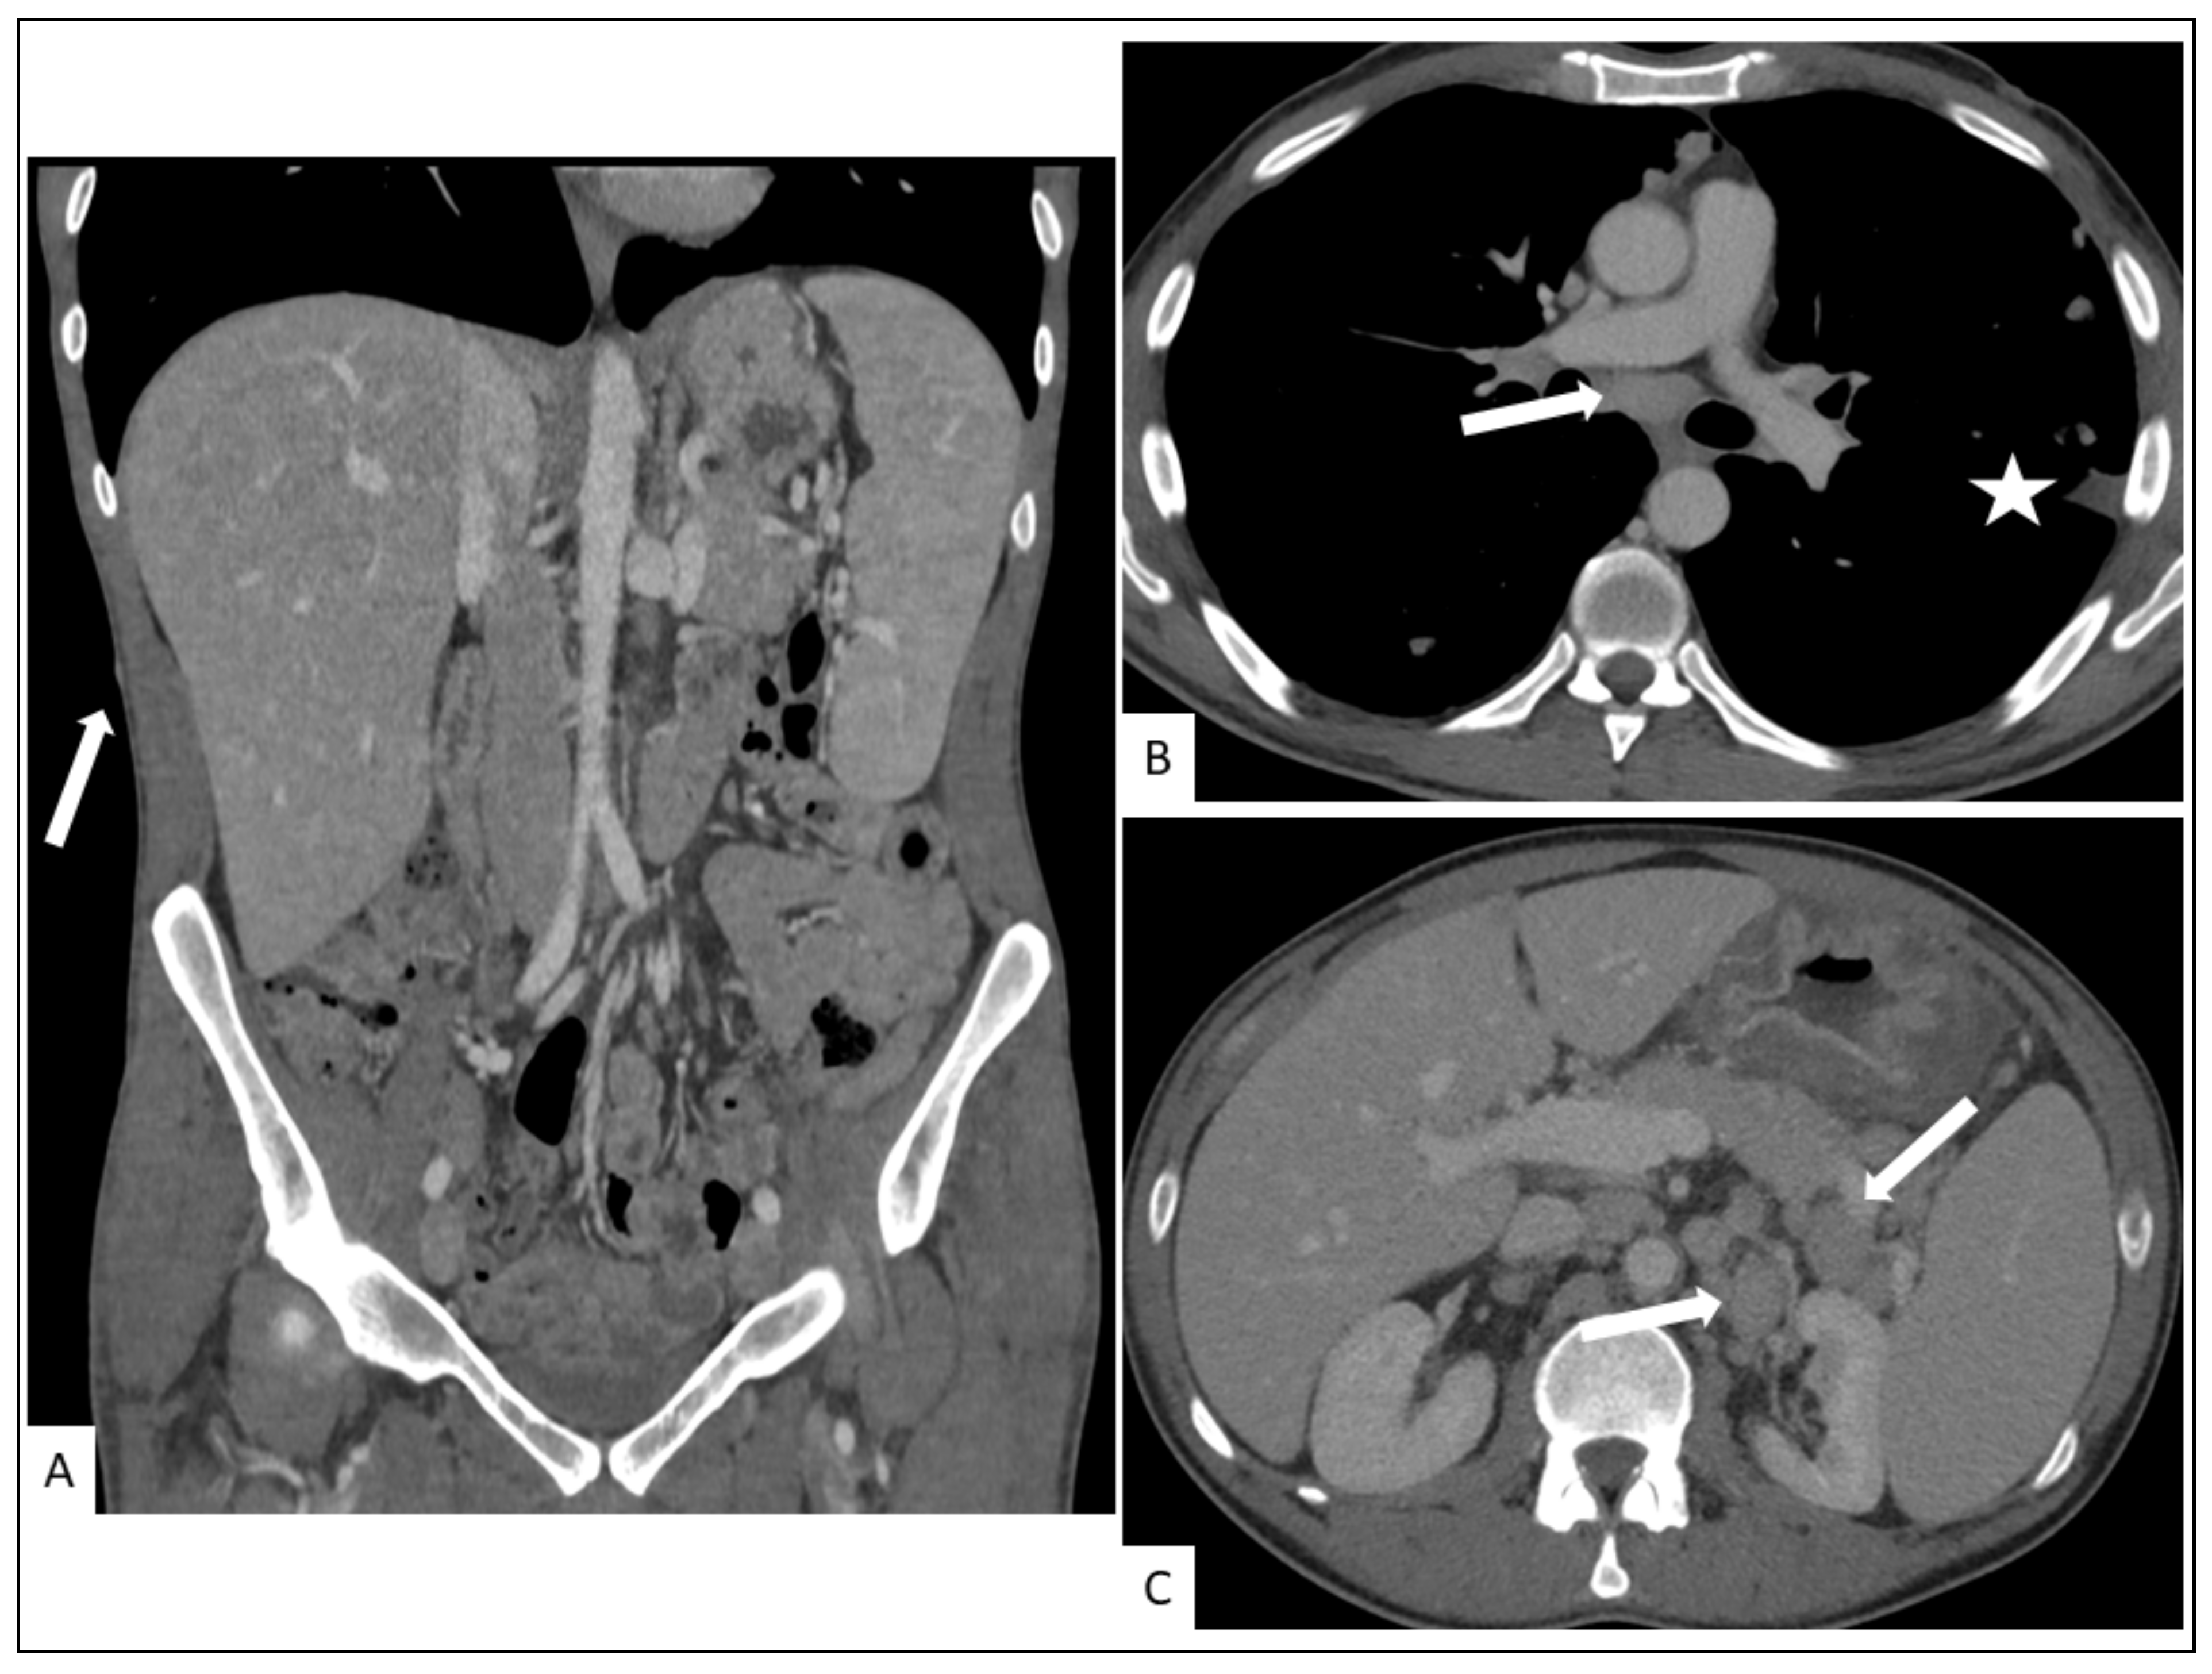

5.2. Hepato-Splenic KS

5.3. Other Visceral Involvement

- Restrepo, C.S.; Martínez, S.; Lemos, J.A.; Carrillo, J.A.; Lemos, D.F.; Ojeda, P.; Koshy, P. Imaging Manifestations of Kaposi Sarcoma. Radiographics 2006, 26, 1169–1185. [Google Scholar] [CrossRef]

- Javadi, S.; Menias, C.O.; Karbasian, N.; Shaaban, A.; Shah, K.; Osman, A.; Jensen, C.T.; Lubner, M.G.; Gaballah, A.H.; Elsayes, K.M. HIV-Related Malignancies and Mimics: Imaging Findings and Management. Radiographics 2018, 38, 2051–2068. [Google Scholar] [CrossRef]